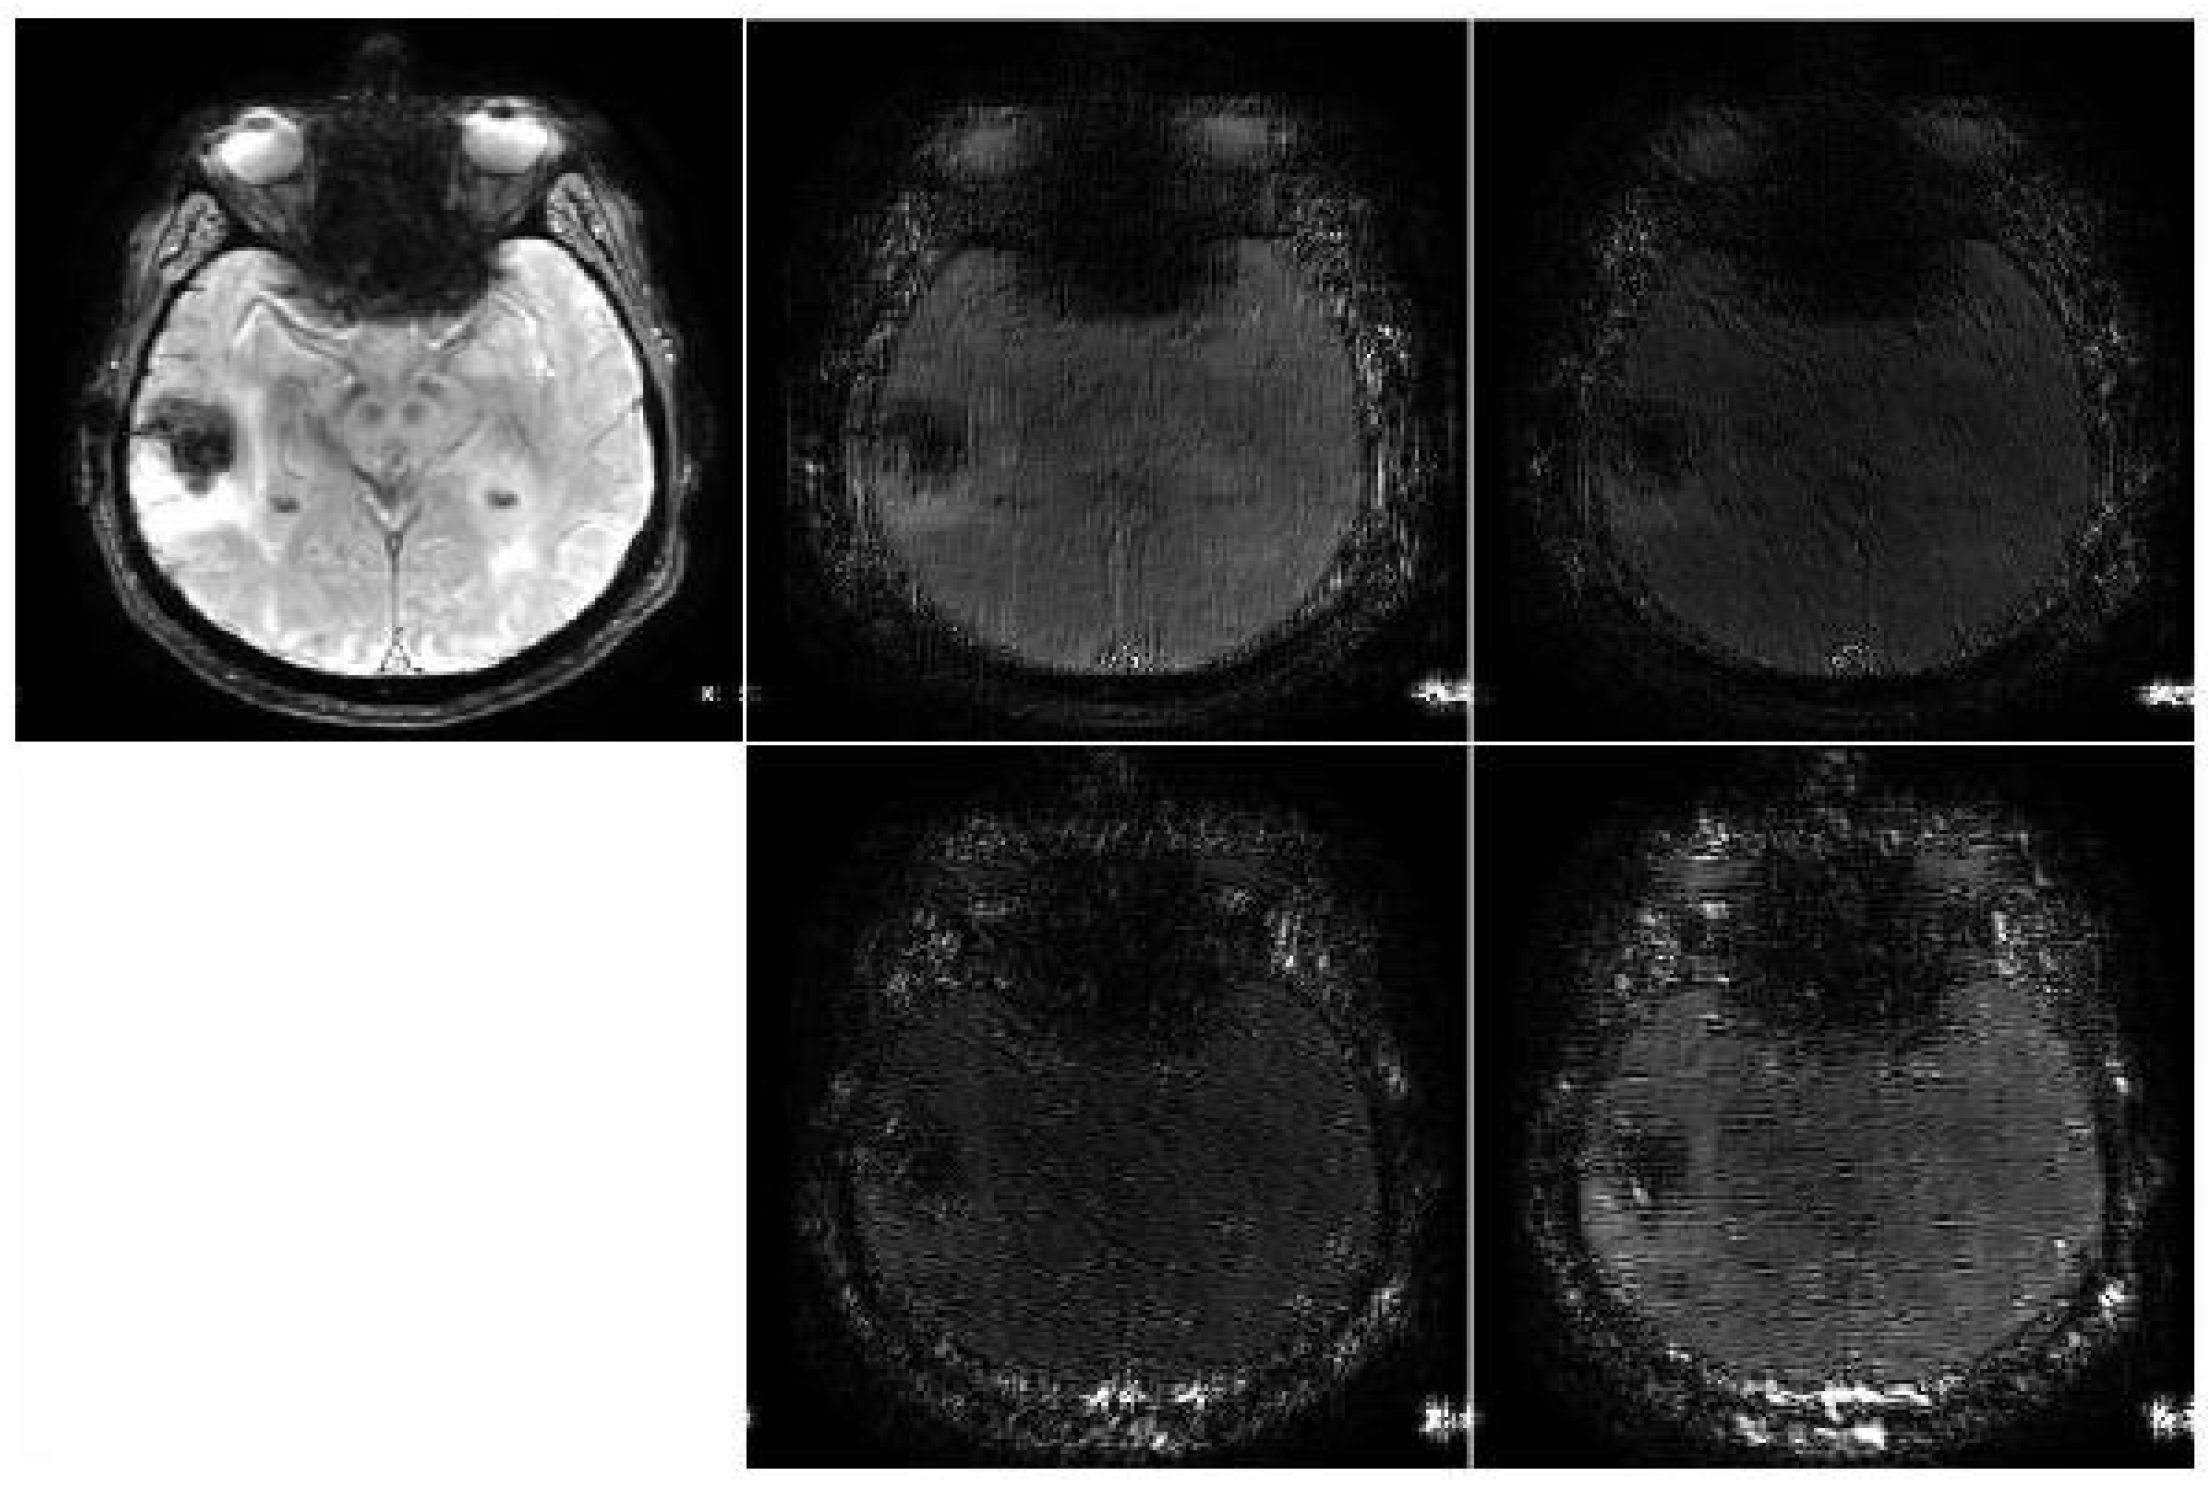

3.1. Dataset and Pre-Processing

3.3. Data Processing and Contourlet Transform